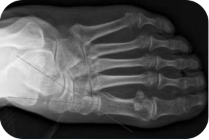

足负重前后位、足负重侧位(足内弓角测量、外弓角测量、跟骨倾斜角)